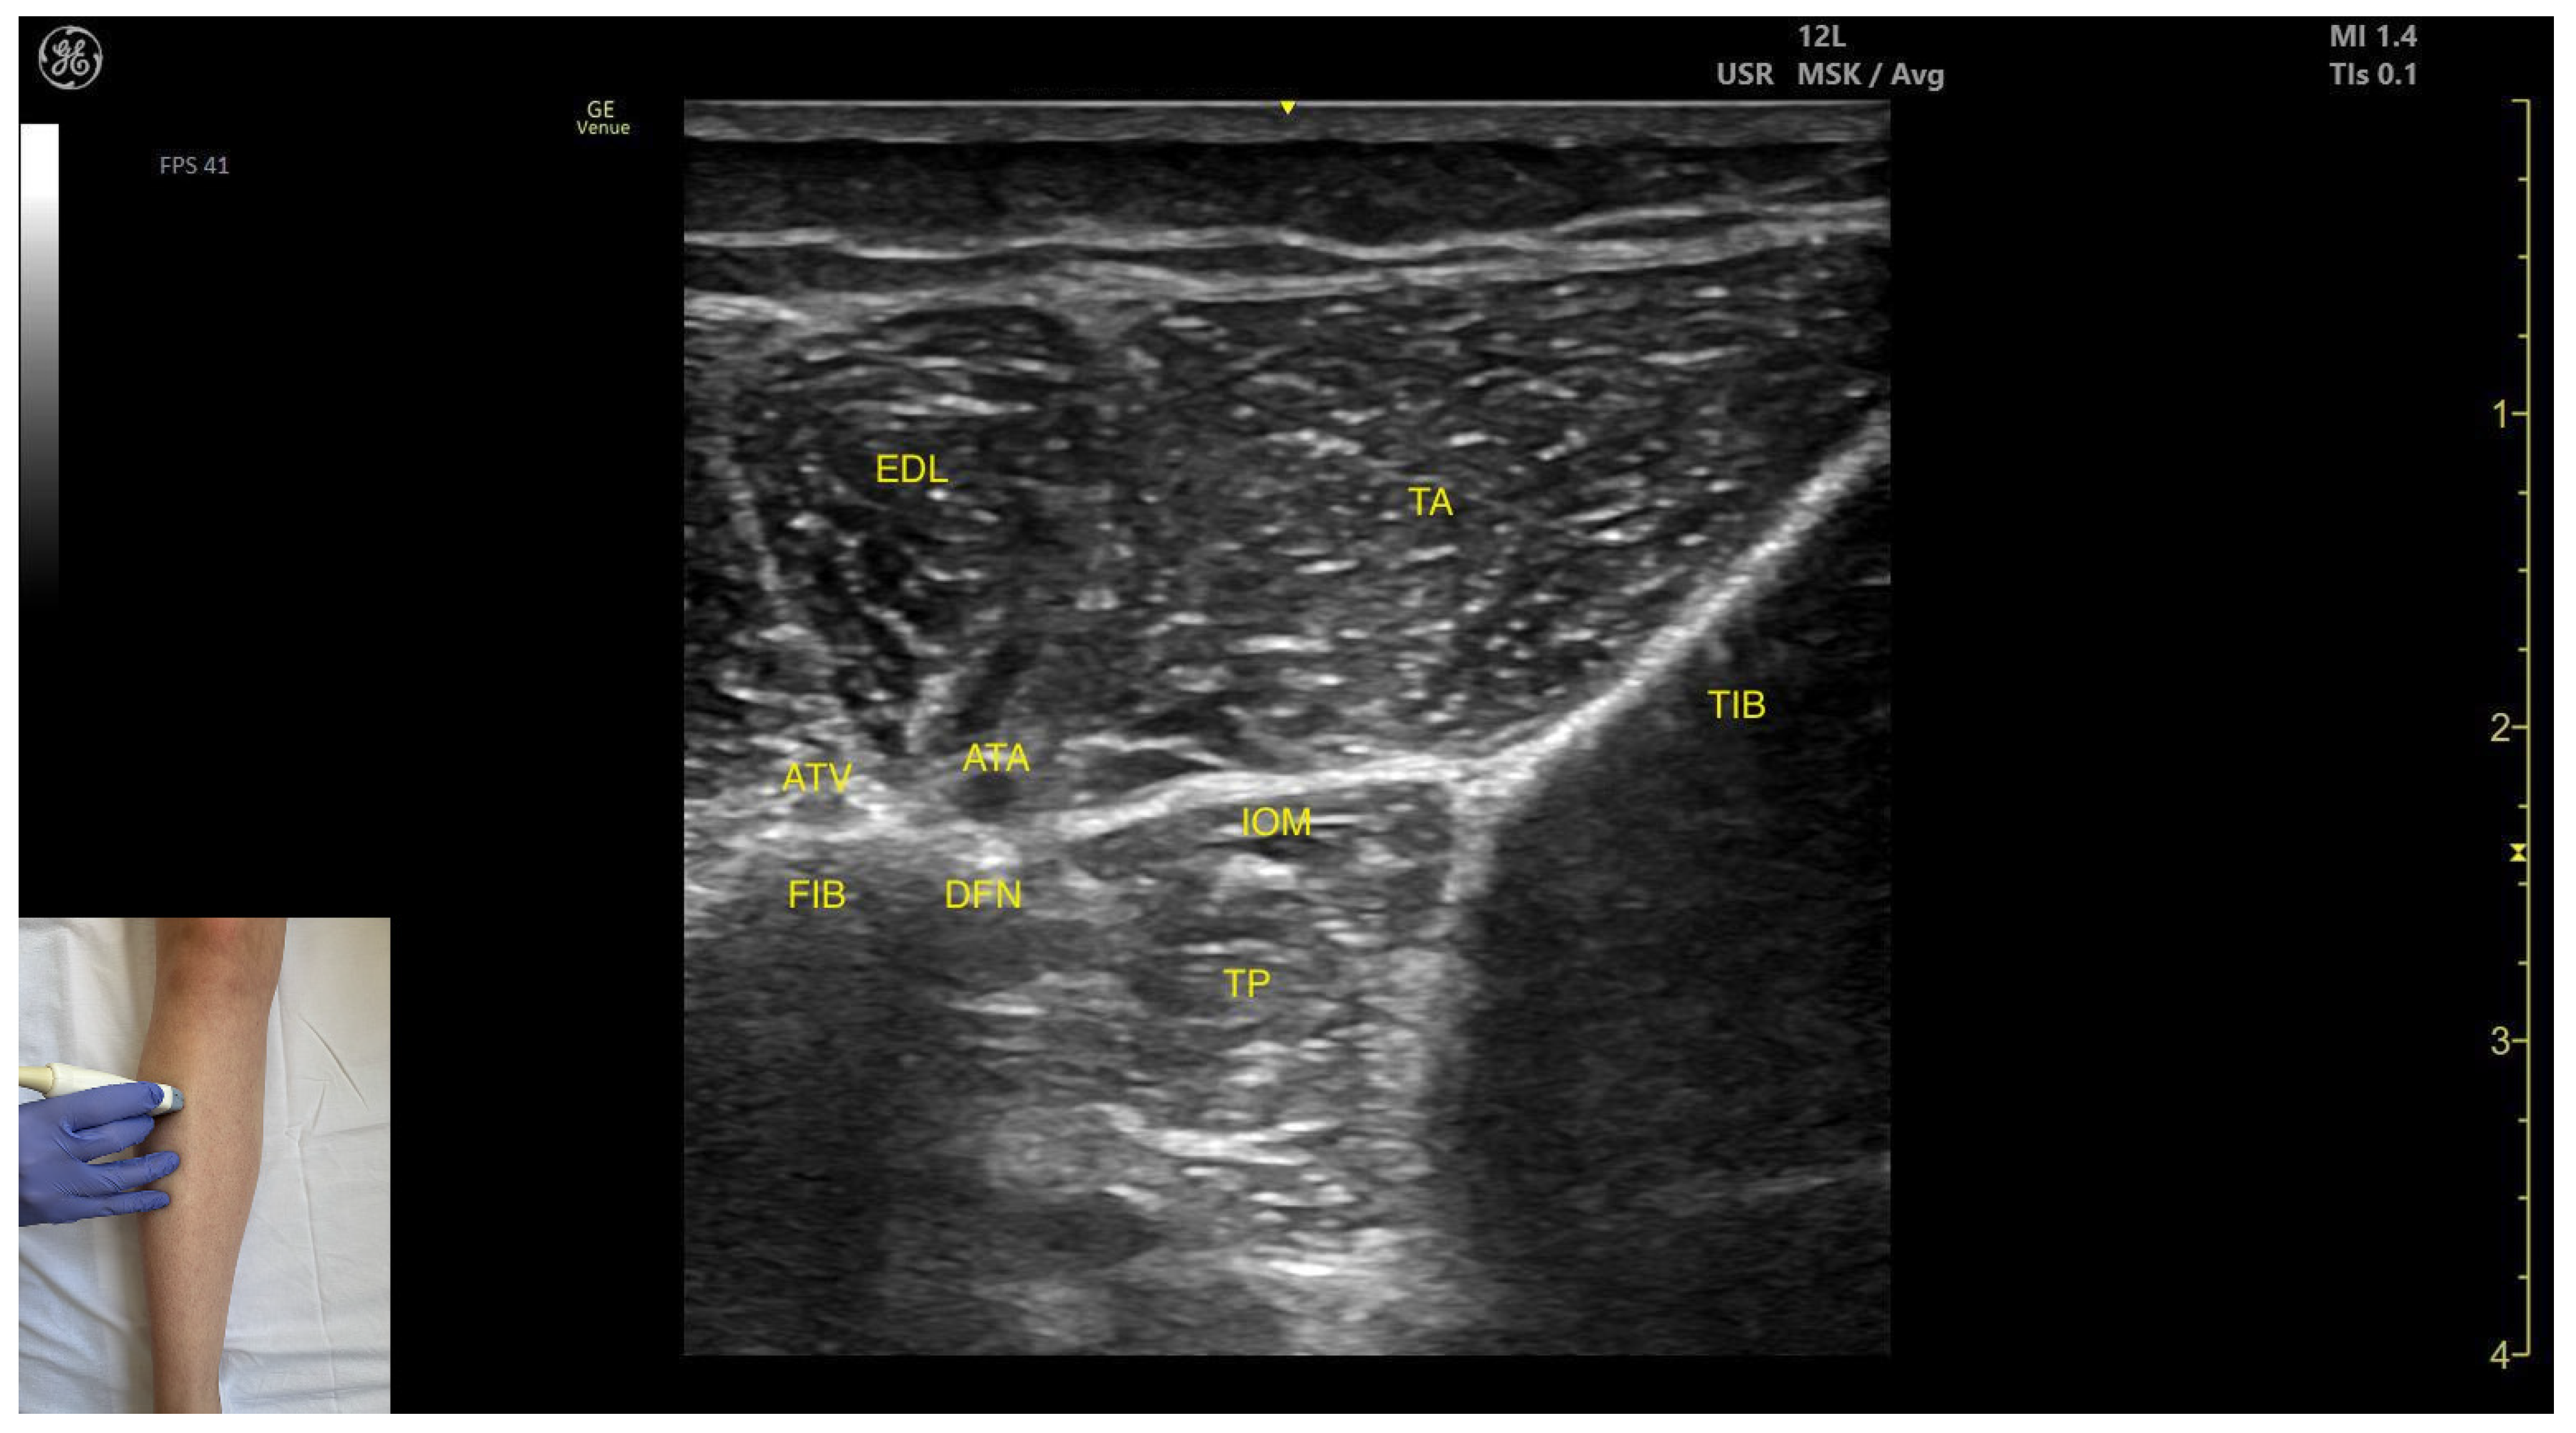

- Muscle position: It is the deepest muscle in the posterior compartment of the leg.

- Neurovascular bundle: Superficial to the interosseous membrane lies the neurovascular bundle composed of the deep peroneal nerve, anterior tibial artery, and anterior tibial vein.

- External fascia: TP has a pronounced fascia that separates it from the tibialis anterior and extensor digitorum longus during BoNT-A injection.

- Dynamic evaluation: During dynamic evaluation muscle contraction is visible during inversion and plantar flexion of the ankle joint.

- Muscle position: It appears as a superficial muscle mass. Deep to the TA lies the interosseous membrane separating it from the tibialis posterior; the extensor digitorum longus lies lateral to the TA.

- External fascia: The TA does not feature a pronounced fascia that separates it from extensor digitorum longus, during BoNT-A injection.

- Dynamic evaluation: During dynamic evaluation, scanning distally toward the ankle, the tibialis anterior decreases in thickness as it transitions into its tendon. Muscle contraction is seen during plantar dorsiflexion and inversion of the ankle joint.

- Muscle position: It occupies the most posterior and lateral position within the anterior compartment of the leg. It lies superficially beneath the subcutaneous plane. Medial to it lies the tibialis anterior; lateral to it lies the fibularis longus.

- Neurovascular bundle: The superficial fibular nerve courses within the intermuscular fascia between the EDL and fibularis longus. Deep structures include the interosseous membrane, tibialis posterior muscle, deep fibular nerve, and the anterior tibial artery.

- External fascia: It presents a pronounced fascia that demarcates it from the superficial plane and adjacent muscles (tibialis anterior and tibialis posterior), aiding in safe BoNT-A injection.

- Dynamic evaluation: During dynamic evaluation, scanning toward the ankle joint, the EDL muscle thickness decreases as the EHL appears deep to it. Muscle contraction is visible during toe extension of digits II–V and dorsiflexion at the ankle joint.

| Tibialis Posterior (anterior window) | ~10 cm distal to the knee joint, in the lateral portion | Interosseous membrane, deep fibular nerve, anterior tibial artery, and anterior tibial vein (superficial); tibialis anterior (superficial and medial), extensor digitorum longus (superficial and lateral); | Transverse scan on the anterior aspect of the leg | Avoid neurovascular injury |

| Tibialis anterior | Proximal third of the anterior aspect of the leg, in the lateral portion | Extensor digitorum longus (lateral); Interosseous membrane, tibialis posterior (deep) | Transverse scan on proximal third of the anterior aspect of the leg | Confirm muscle position and relations |

| Extensor Digitorum Longus | Proximal third of the anterior aspect of the leg, in the lateral portion | Tibialis anterior (medial); Fibularis longus (lateral); superficial fibular nerve, anterior tibial artery, deep fibular nerve (deep) | Transverse scan on proximal third of the anterior aspect of the leg | Visualize extensor digitorum longus as most superficial muscle and confirm muscle position and relations |